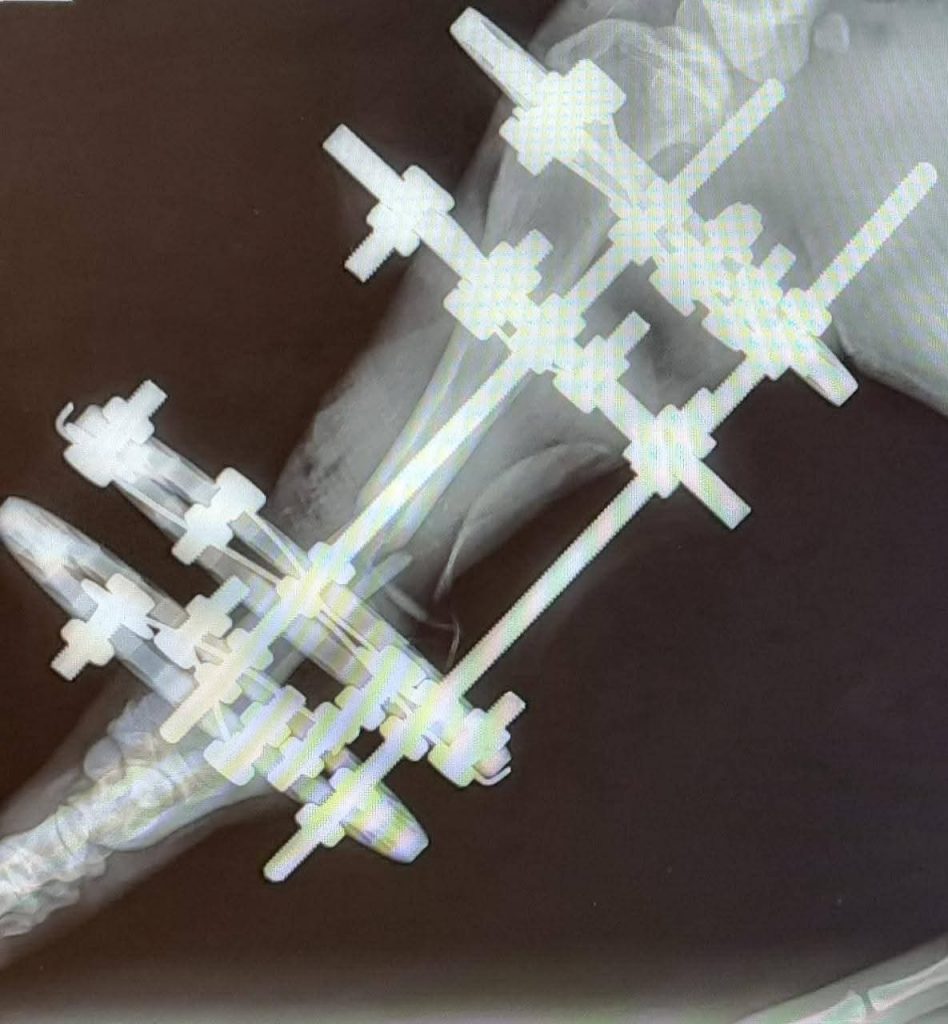

Orso ist in Italien verunfallt, dabei wurden seine beiden Hinterläufe zertrümmert. Er wurde in einer Klinik wieder zusammengesetzt und braucht jetzt in Deutschland eine Pflegestelle – uns! 🙂